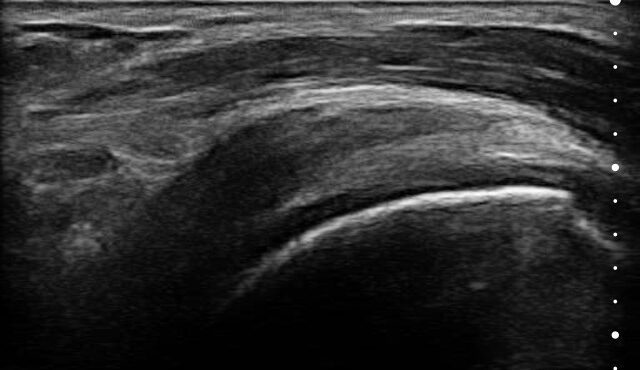

Visualize targets in real time to deliver PRP or cortisone—even in complex joints. Instantly diagnose sprains, tears, and effusions, and make confident decisions about surgical intervention